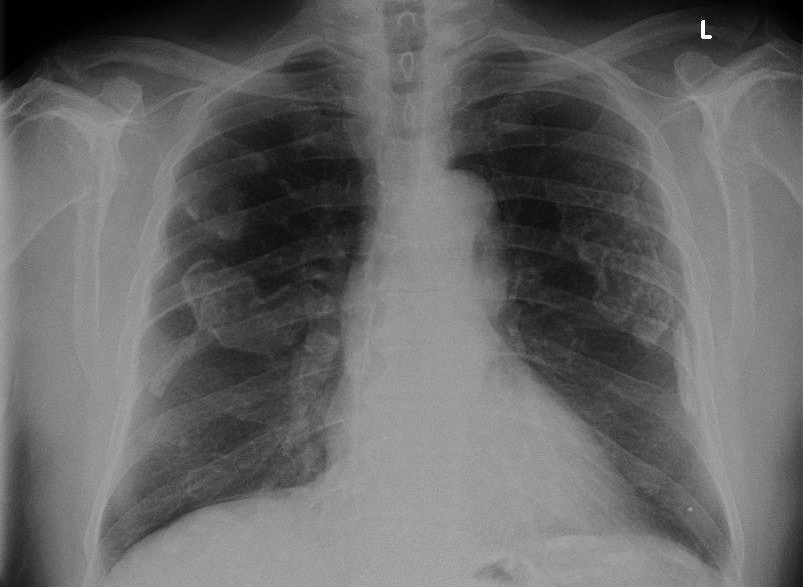

What is the abnormality that can be seen in this erect chest x-ray

Pleural plaques - seen as irregular lesions bilaterally

Pleural plaques are a consequence as an exposure to what substance?

Pleural plaques are a consequence of asbestos inhalation and develop over 2 to 4 decades from exposure